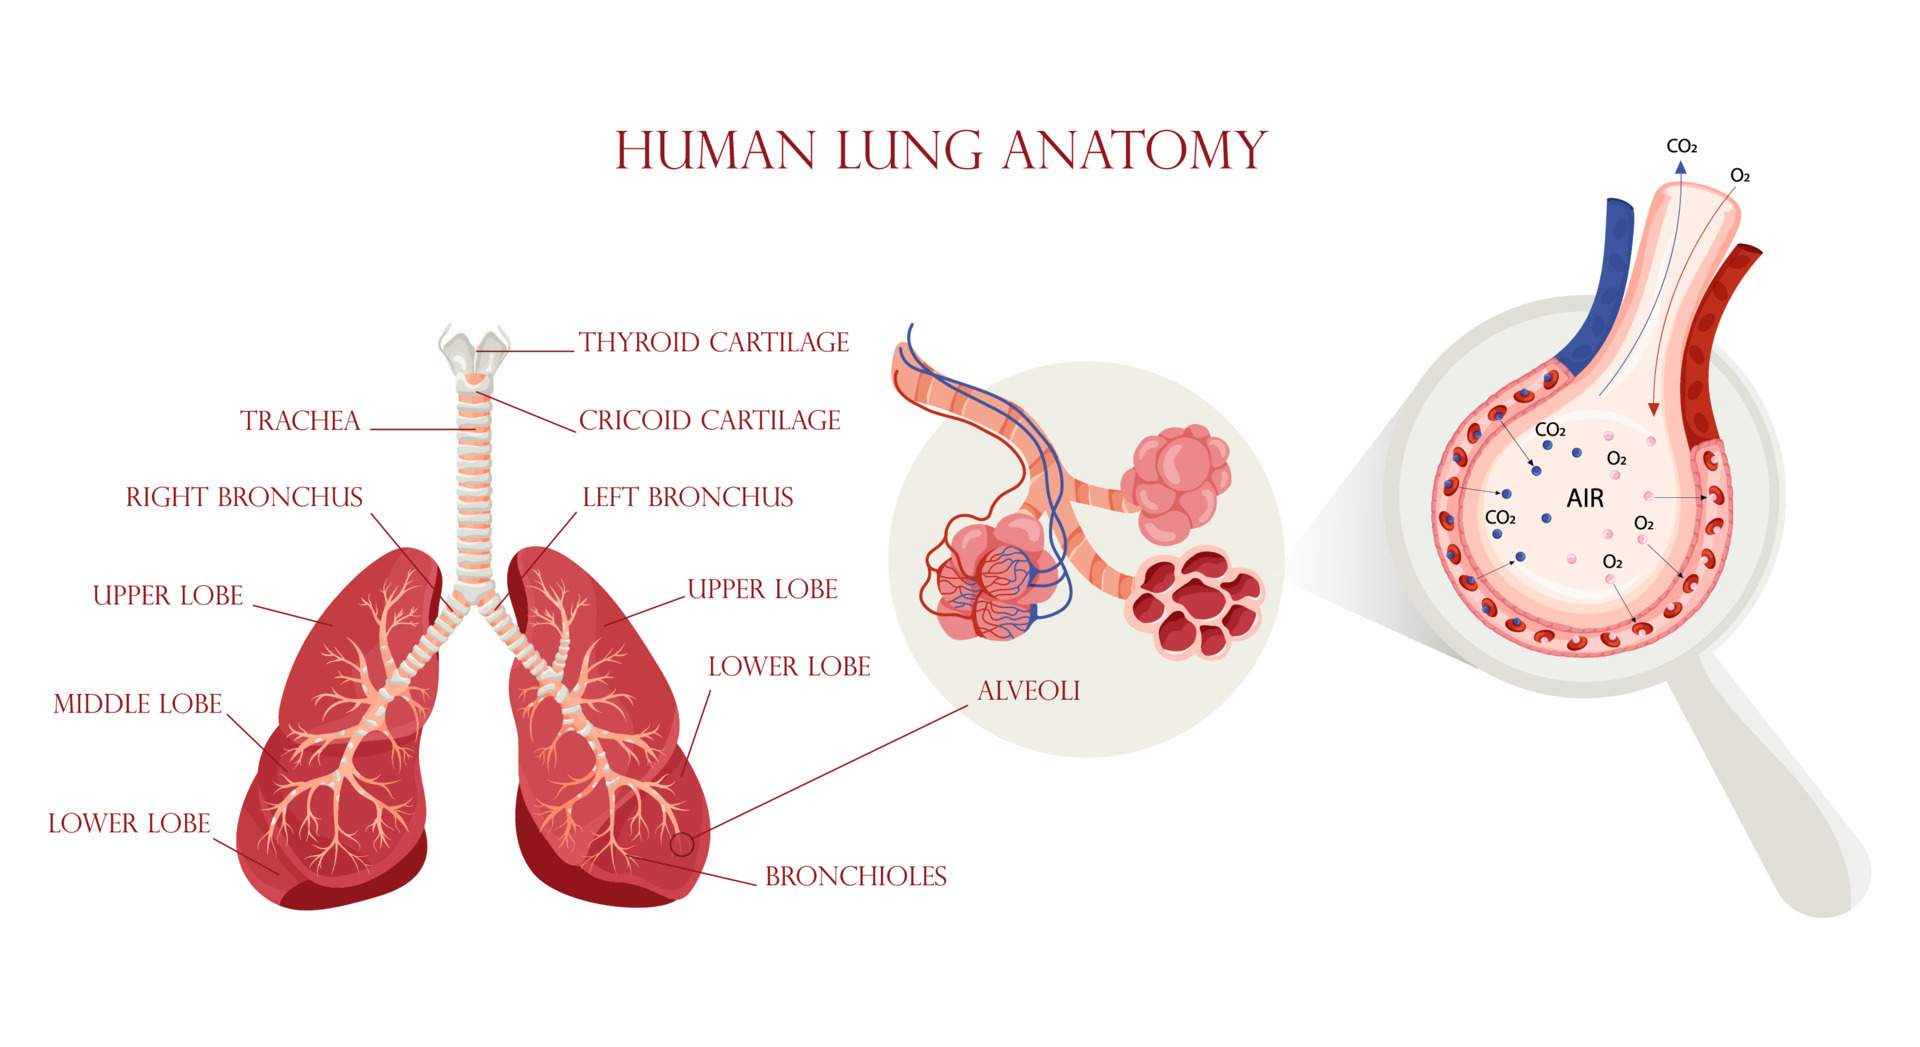

Lung Anatomy & Function - Lung Nodule, Lung Disease And Lung Infection

healthjade.com

healthjade.com

alveoli lung lungs gas exchange pulmonary anatomy alveolus membrane blood structure respiratory function microscopic supply infection disease